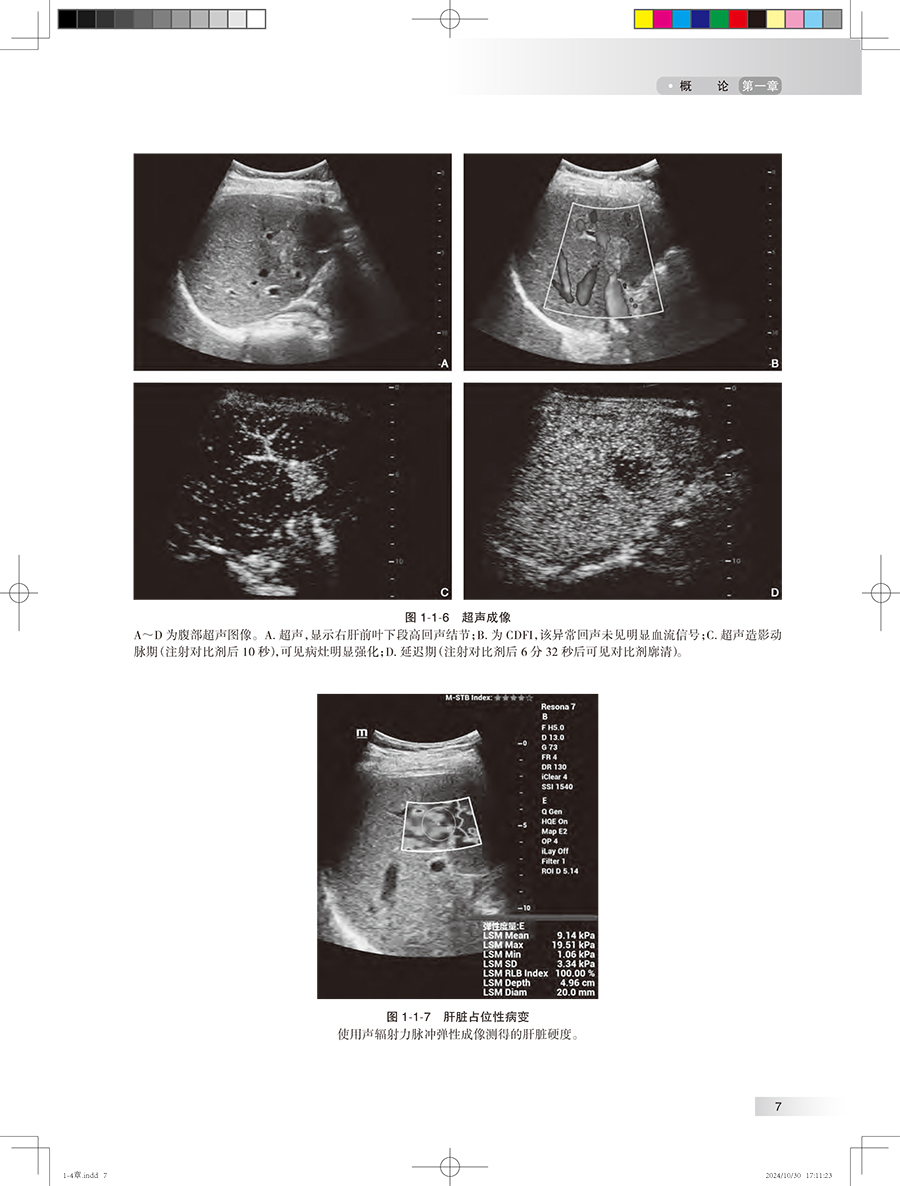

第一章 概 论/1 第一节 肝脏解剖、病理生理、疾病发病情况、影像学的价值 / 1 一、 肝脏解剖/1 二、 肝脏病理生理 / 3 三、 肝脏常见疾病的发病情况 / 3 四、 影像学的价值 / 6 第二节 胆道解剖、病理生理、疾病发病情况、影像学的价值 / 18 一、 胆道解剖/18 二、 胆道病理生理 / 20 三、 胆道系统常见疾病的发病情况/20 四、 影像学的价值 / 23 第三节 胰腺解剖、病理生理、疾病发病情况、影像学的价值 / 26 一、 胰腺解剖/26 二、 胰腺病理生理 / 27 三、 胰腺常见疾病的发病情况 / 27 四、 影像学的价值 / 29 第四节 脾脏解剖、病理生理、疾病发病情况、影像学的价值 / 35 一、 脾脏解剖/35 二、 脾脏病理生理 / 37 三、 脾脏常见疾病的发病情况 / 37 四、 影像学的价值 / 38 第五节 消化道解剖、病理生理、疾病发病情况、影像学的价值 / 42 一、 消化道解剖/42 二、 消化道病理生理 / 44 三、 消化道常见疾病的发病情况/45 四、 影像学的价值 / 46 第二章 临床症状 / 体征/54 第一节 腹痛/54 一、 腹痛的发生机制 / 54 二、 腹痛的分类及病因 / 54 三、 腹痛的临床表现 / 54 四、 腹痛的伴随症状 / 57 五、 影像学检查在腹痛诊断中的应用/57 六、 腹痛的诊断思路 / 58 第二节 腹胀/59 一、 腹胀的发生机制 / 59 二、 腹胀的分类与病因 / 59 三、 腹胀的临床表现 / 59 四、 腹胀的伴随症状 / 60 五、 腹胀的诊治思路 / 60 六、 影像学检查在腹胀诊断中的应用/61 第三节 呕吐/62 一、 定义及概述/62 二、 临床表现及诊断检查 / 63 三、 影像学在呕吐中的应用 / 63 第四节 腹泻/66 一、 定义及概述/66 二、 临床表现与诊断检查 / 66 三、 影像学在腹泻中的应用 / 67 第五节 反酸/70 一、 定义及概述/70 二、 临床表现与诊断检查 / 71 三、 影像学在反酸中的应用 / 72 第六节 嗳气/73 一、 定义及概述/73 二、 临床表现与诊断检查 / 74 三、 影像学在嗳气中的应用 / 74 第七节 吞咽困难/75 一、 定义及概述/75 二、 临床表现与诊断检查 / 76 三、 影像学在吞咽困难中的应用/77 第八节 黄疸/78 一、 定义及概述/78 二、 临床表现与诊断检查 / 78 三、 影像学在黄疸中的应用 / 79 第九节 呕血/81 一、 定义及概述/81 二、 临床表现与诊断检查 / 81 三、 影像学在呕血中的应用 / 83 第十节 便血/83 一、 定义及概述/83 二、 临床表现与诊断检查 / 84 三、 影像学在便血中的应用 / 85 第三章 肝脏影像常见征象 / 86 第一节 肝脏形态改变 / 86 一、 肝脏肿大/86 二、 肝脏缩小/91 三、 肝叶比例失调 / 94 四、 肝裂增宽/96 五、 獭尾肝/99 六、 扇贝征/101 七、 肝包膜回缩征 / 105 第二节 肝脏密度改变 / 110 一、 CT 平扫低密度 / 110 二、 CT 平扫高密度 / 115 三、 地图征/118 四、 龟背征/119 第三节 肝脏信号改变 / 120 一、 T 1WI 高信号 / 120 二、 T 1WI 低信号 / 122 三、 T 2WI 高信号 / 123 四、 T 2WI 低信号 / 125 五、 含脂病灶/127 六、 结中结/129 七、 马赛克征 / 镶嵌征 / 130 八、 门脉周围晕征 / 131 九、 簇状征/132 十、 棒棒糖征/133 十一、 靶征/135 十二、 飘带征 / 水上浮莲征 / 141 十三、 灯泡征/142 十四、 蜘蛛网征/146 十五、 轮辐征/148 十六、 繁星征/149 十七、 环礁征/151 第四节 局灶性病变强化特征 / 153 一、 速升速降/153 二、 速升缓降/156 三、 缓升缓降/160 四、 延迟强化/161 五、 环形强化/167 六、 暂时性肝脏密度 / 信号差异 / 172 七、 周边廓清征/176 八、 血管穿行征/180 九、 翻转征/184 十、 三叶草征/187 十一、 肝胆细胞期低信号 / 191 十二、 肝胆细胞期高信号 / 198 第五节 血管改变/209 一、 门静脉积气/209 二、 轨道征/211 三、 充盈缺损/212 四、 动静脉分流/214 五、 门腔静脉分流 / 217 六、 门静脉海绵样变 / 218 七、 肝静脉早显/221 八、 肝窦阻塞综合征 / 222 第四章 胆道系统影像常见征象 / 231 第一节 胆道病变/231 一、 肝内胆管扩张 / 231 二、 肝外胆管扩张 / 246 三、 肝内外胆管扩张 / 249 四、 胆管狭窄/261 五、 胆管壁增厚/268 六、 胆管肿块/275 七、 胆道积气/279 八、 剪枝征/281 九、 串珠征/282 十、 软藤征/284 十一、 杯口征/286 十二、 双管征/287 十三、 四管征/289 十四、 靶征/291 十五、 云雾征/292 十六、 中心点征/294 十七、 鸟嘴征/296 第二节 胆道病变/299 一、 胆囊肿大/299 二、 胆囊萎缩/300 三、 弥漫性胆囊壁增厚 / 302 四、 局限性胆囊壁增厚 / 305 五、 小帽征/307 六、 珍珠项链征/309 七、 瓷样胆囊/311 八、 隔膜胆囊/312 九、 双胆囊/314 十、 游离胆囊/315 十一、 高位胆囊管 / 316 十二、 低位胆囊管 / 316 十三、 胆囊窝肿块 / 319 第五章 胰腺影像常见征象 / 324 第一节 胰腺形态改变 / 324 一、 胰腺肿大/324 二、 胰腺萎缩/328 三、 胰腺局部凸起 / 332 四、 环状胰腺/336 五、 哑铃形胰腺/337 六、 分叶胰腺/338 七、 胰腺分裂/339 八、 腊肠征/340 九、 胶囊征/341 第二节 胰腺密度改变 / 343 一、 CT 平扫低密度 / 343 二、 CT 平扫高密度 / 349 三、 钙化/353 第三节 胰腺信号改变 / 359 一、 T 1WI 高信号 / 359 二、 T 1WI 低信号 / 365 三、 T 2WI 高信号 / 376 四、 T 2WI 低信号 / 386 第四节 胰管改变/398 一、 胰管扩张/398 二、 胰管狭窄/402 三、 胰管穿行 / 穿透征 / 402 四、 胰管截断征/402 五、 胰管串珠征/404 六、 胰管不相交征 / 405 第五节 肿块/406 一、 富血供肿块/406 二、 乏血供肿块/409 三、 囊性肿块/413 四、 囊实性肿块/419 五、 葡萄征/423 六、 蜂窝征/424 七、 血管穿行征/427 八、 包膜征/430 九、 浮云征/433 第六章 脾脏影像常见征象 / 437 第一节 脾脏形态改变 / 437 一、 脾肿大/437 二、 脾皮质边缘征 / 439 三、 脾楔形不强化区 / 441 第二节 脾脏信号密度特征 / 443 一、 花斑脾/443 二、 脾脏密度增加 / 444 三、 岩石脾/445 四、 脾裂隙征/447 五、 脾包膜钙化/448 六、 T 2WI 灯泡征 / 449 七、 脾气泡征(气 - 液平面) / 452 第七章 食管影像常见征象 / 456 第一节 食管管腔改变 / 456 一、 管腔狭窄/456 二、 管腔扩张/458 三、 鸟嘴征 / 萝卜根征 / 460 四、 三环征/462 五、 腔内异常/463 第二节 管壁改变/465 一、 管壁隆起/465 二、 管壁凹陷/467 三、 管壁增厚/470 四、 管壁僵硬/472 五、 充盈缺损/474 六、 龛影/476 七、 憩室/478 第三节 黏膜改变/480 一、 黏膜破坏/480 二、 黏膜平坦/481 三、 黏膜增宽和迂曲 / 483 四、 环形征/485 第四节 腔外改变/487 一、 食管压迹/487 二、 脂肪间隙异常 / 490 三、 管壁外积气/492 第八章 胃影像常见征象 / 495 第一节 胃腔改变/495 一、 胃腔扩张/495 二、 胃腔缩小/498 三、 葫芦形胃 / 哑铃形胃 / 503 四、 皮革胃/504 五、 胃扭转/506 六、 双泡征/508 第二节 胃壁改变/510 一、 胃壁隆起/510 二、 胃壁凹陷/515 三、 胃壁增厚/518 四、 胃壁僵硬/527 五、 胃壁积气/531 六、 胃壁水肿/532 七、 胃壁肿块/534 八、 龛影/536 九、 充盈缺损/539 十、 憩室/541 第三节 黏膜改变/544 一、 黏膜破坏/544 二、 黏膜平坦/546 三、 黏膜增宽和迂曲 / 547 四、 黏膜纠集/549 第四节 其他改变/550 一、 半月征/550 二、 狭颈征/552 三、 项圈征/554 四、 指压征 / 裂隙征/555 五、 环堤征/557 六、 肩胛征 / 袖口征/560 第九章 肠管影像常见征象 / 565 第一节 肠腔改变/565 一、 肠腔扩张/565 二、 动脉瘤样扩张 / 567 三、 肠腔狭窄/568 四、 肠腔高密度/571 五、 靶环征/572 六、 鹅颈征/574 七、 苹果核征/575 八、 铅管征/577 九、 咖啡豆征/578 十、 鸟嘴征/580 十一、 堆硬币征/581 十二、 哨兵袢征/584 第二节 肠壁改变/587 一、 肠壁增厚/587 二、 肠壁肿块/595 三、 肠壁气体/601 四、 分层强化(三明治征)/604 五、 肠壁憩室/606 六、 肠壁囊性 / 囊实性病变 / 608 七、 肠壁穿孔/611 八、 肠壁溃疡/614 九、 指压痕征(缺血坏死性肠炎)/616 十、 鹅卵石 / 铺路石征 / 617 第三节 肠系膜改变 / 620 一、 梳齿征/620 二、 漩涡征/623 三、 肠系膜混浊征 / 626 四、 缆绳征/629 五、 肠系膜污垢征 / 630 六、 结肠旁高密度环征(肠脂垂)/632 七、 脂肪晕征/634 八、 手风琴征/635 九、 腹茧症/638 十、 脂肪条纹征/641 十一、 脂肪环征/643 中英文名词对照索引/646 登录中华临床影像征象库步骤 / 650